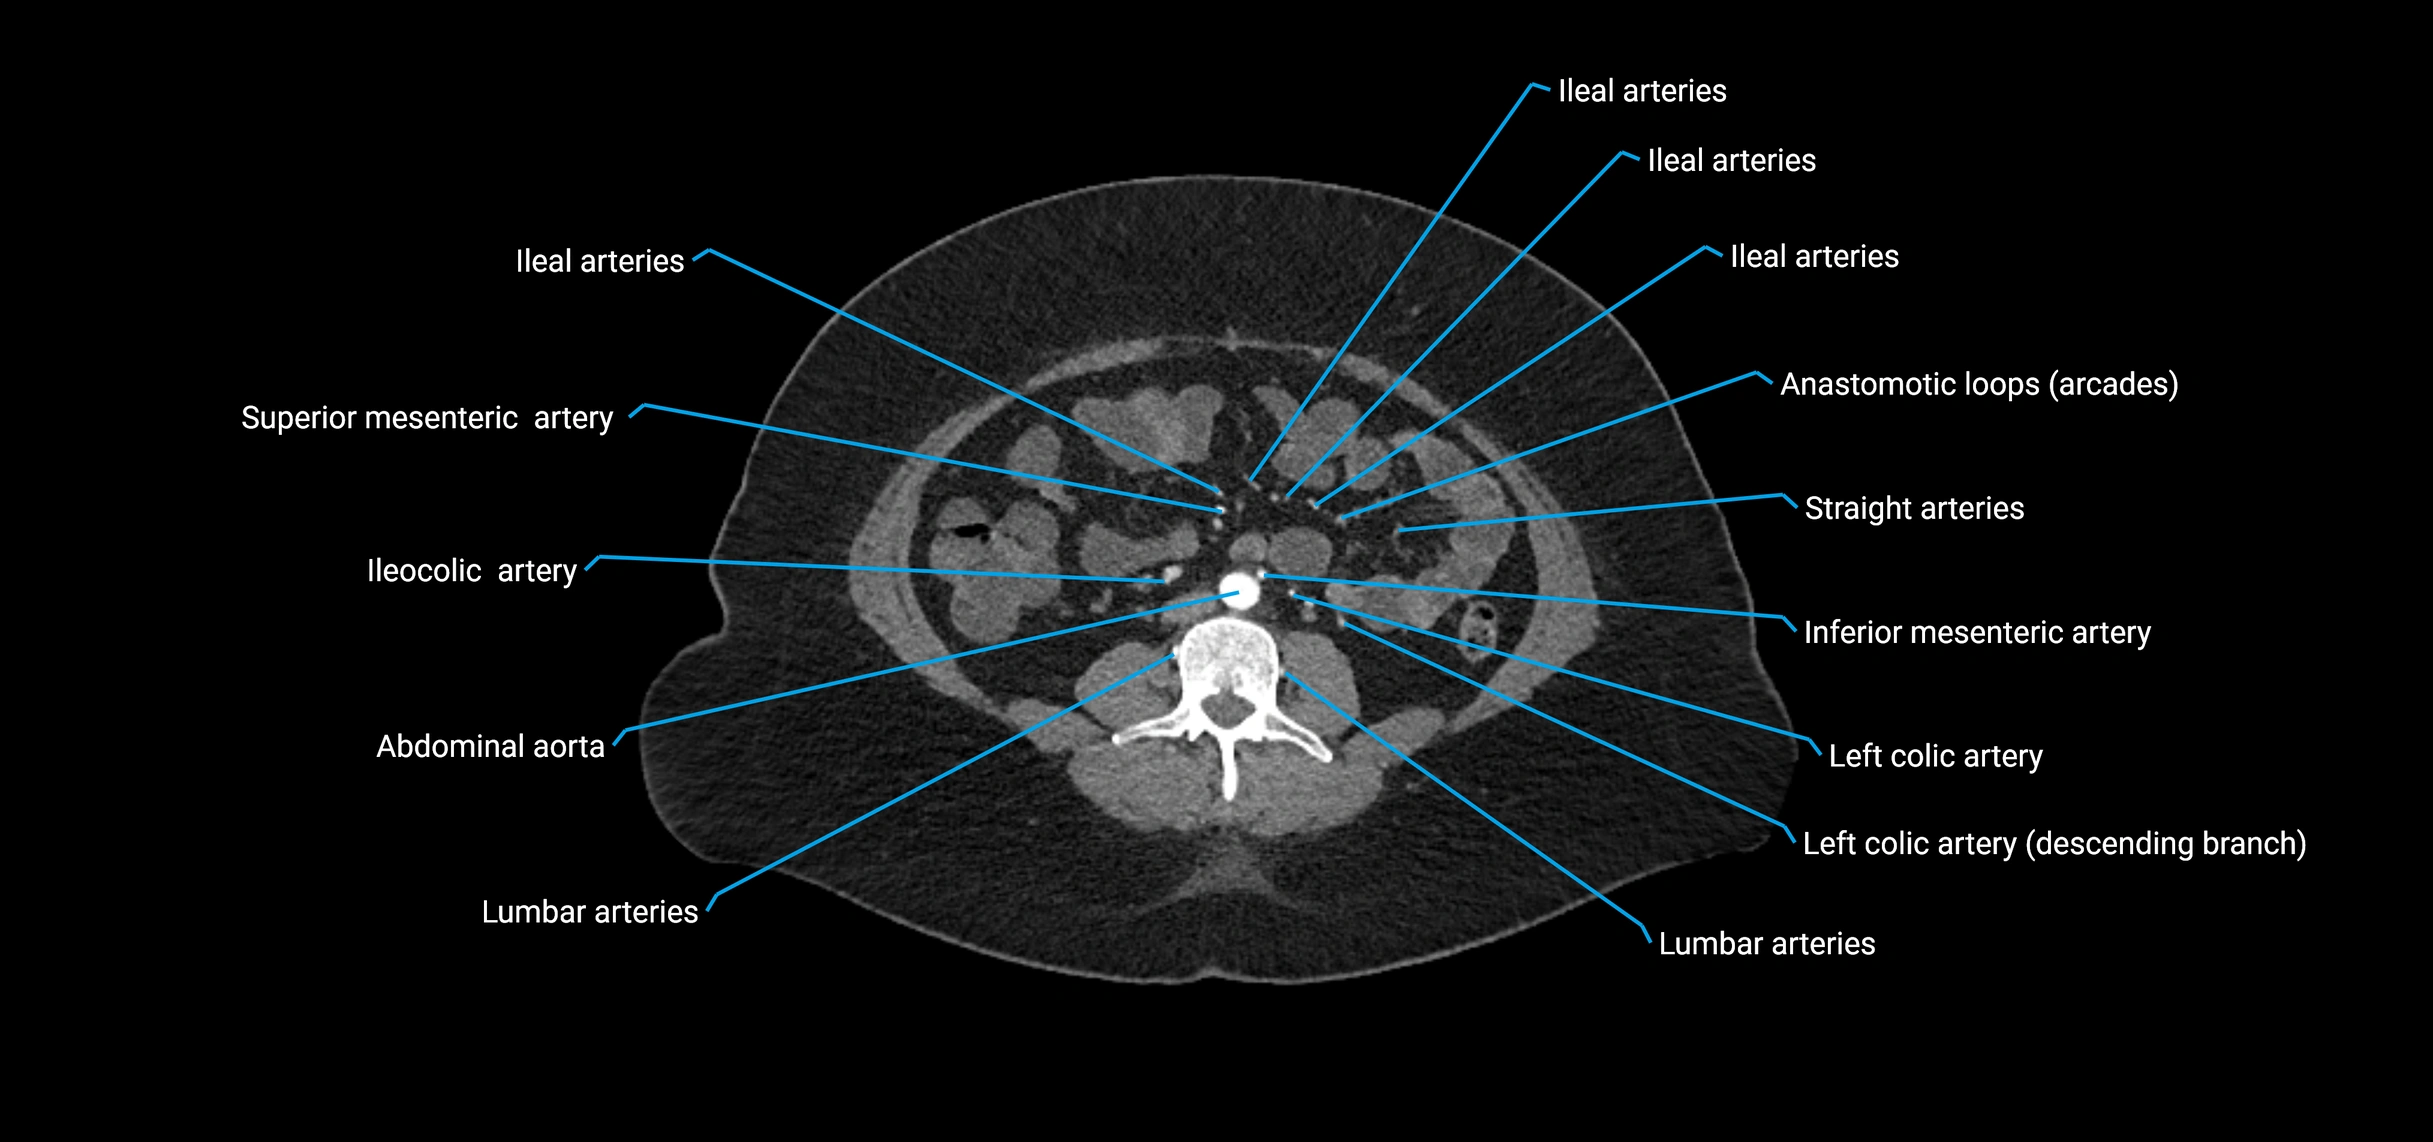

Branches

• Unpaired visceral branches: celiac trunk, superior mesenteric artery (SMA), inferior mesenteric artery (IMA)

• Paired visceral branches: middle suprarenal arteries, renal arteries, gonadal arteries (testicular or ovarian)

• Parietal branches: inferior phrenic arteries, lumbar arteries, median sacral artery

• Terminal branches: right and left common iliac arteries

Contrast-enhanced CT (CTA):

• Gold standard for abdominal aortic imaging

• Provides excellent detail of lumen, wall, aneurysm, thrombus, and branch vessels

• Multiplanar and 3D reconstructions help in aneurysm measurement, stent graft planning, and dissection evaluation

• Detects acute rupture, traumatic injury, or occlusion with high sensitivity

CT images

image